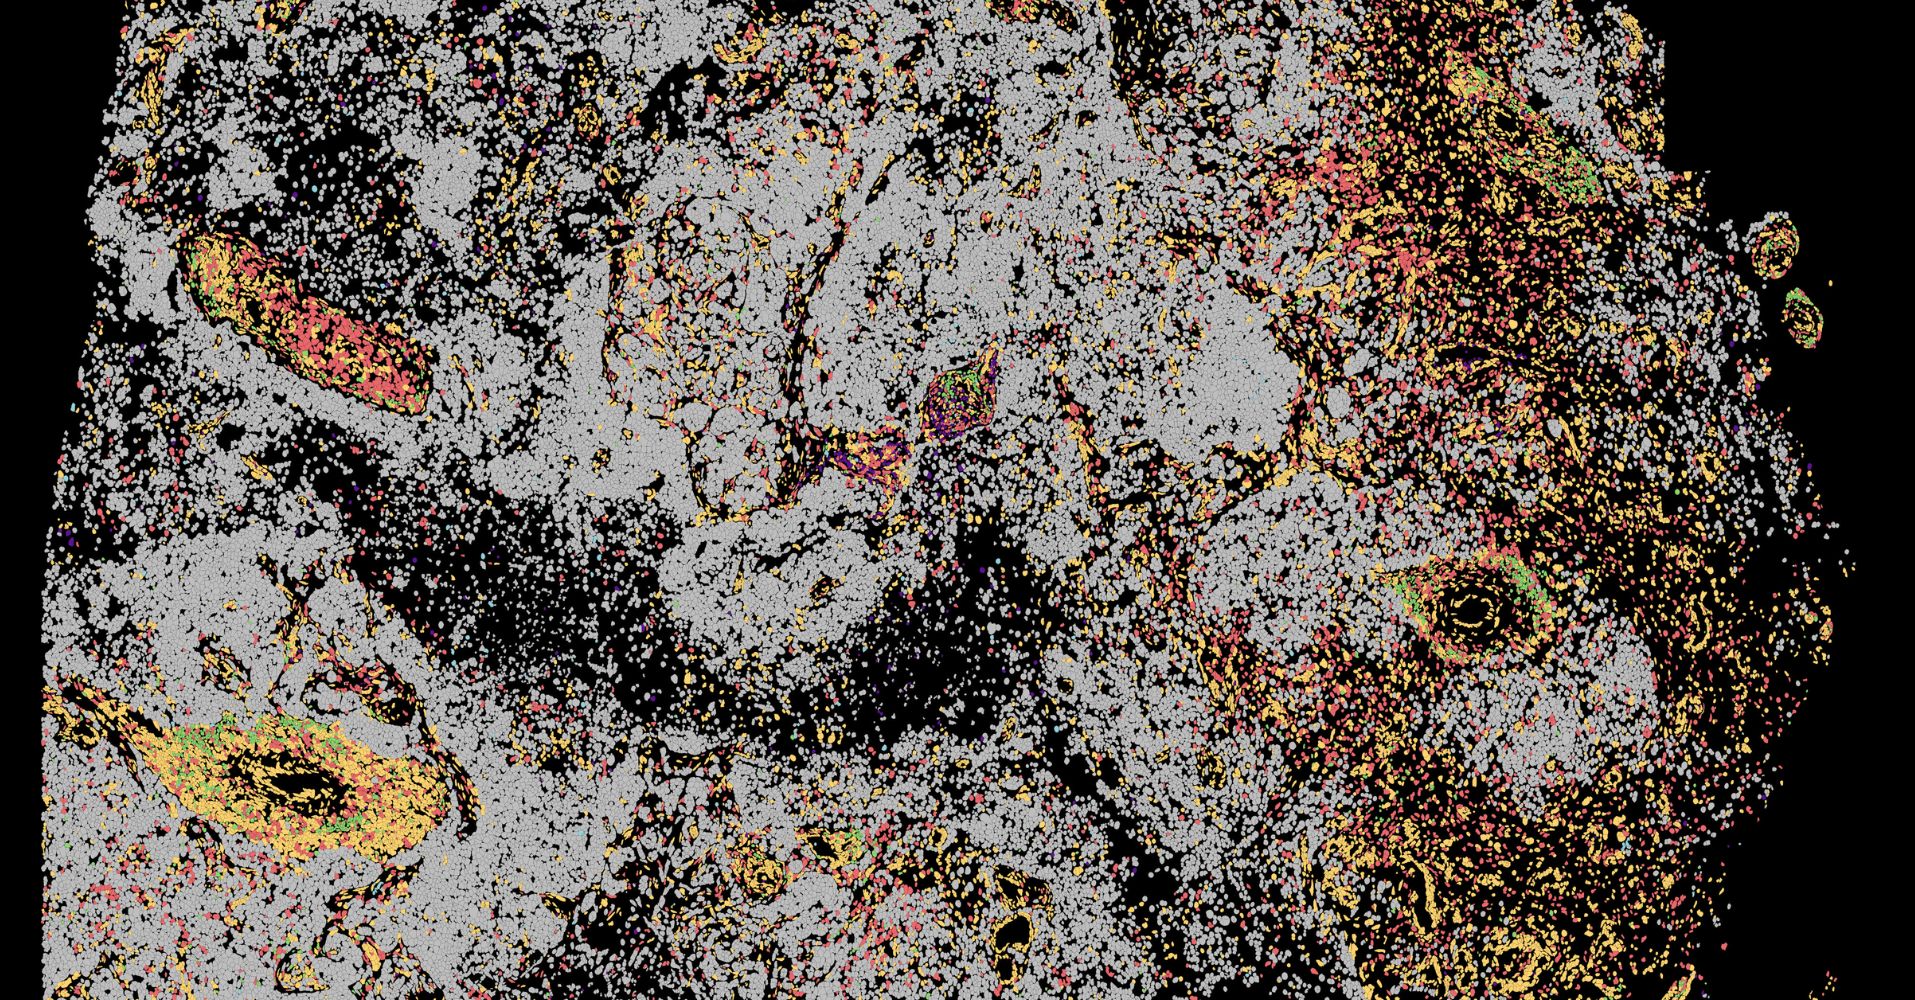

- After unveiling the cellular atlas of the human tonsil, CNAG now takes a further step with the release of its spatial transcriptomics m